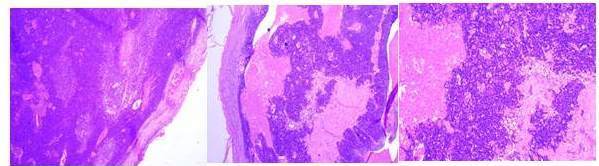

La revisión realizada por servicio de anatomía patología de nuestro centro, evidencia un nódulo con capsula fibrótica que muestra en su interior un carcinoma de células escamosas de aspecto basaloide con áreas sólidas y quísticas (Figura 5).

No observan tejido ganglionar linfático remanente, por lo que infieren que los hallazgos son compatibles con neoplasia primaria originaria de un quiste branquial complementando con realización de estudio de inmunohistoquímica, el cual resultó positivo para citoqueratina 34BE12, P63 y citoqueratina 7.